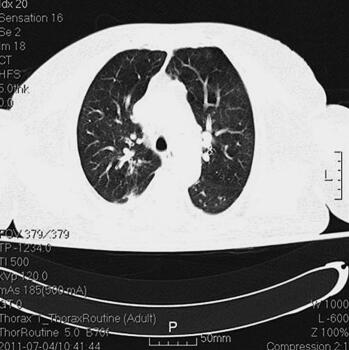

诊治经过:入院后留置右锁骨下深静脉导管,监测CVP。患者血压逐渐平稳,停用多巴胺。继续机械通气,头孢哌酮-舒巴坦钠针剂及阿奇霉素针剂联合抗感染,甲泼尼龙及多索茶碱解痉平喘,改善微循环,化痰等对症支持治疗。并予肠内营养,胰岛素微泵控制血糖。复查胸部CT(7月4日)(图2),感染较前明显吸收;复查(7月4日)CRP 10mg/L,PCT 0.22ng/ml。

图2 胸部CT(7月4日),感染较前明显吸收